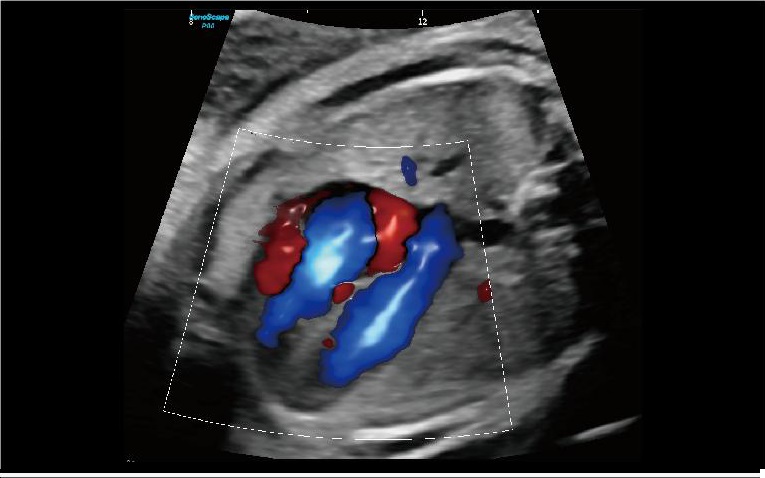

STIC

Zamansal ve mekânsal boyutlar boyunca frame ratelerin ortalamasını alarak, STIC farklı düzlemlerde görüntüler oluşturur; böylece hızla hareket eden fetal kalp yapılarını farklı açılardan kapsamlı bir şekilde inceleme ve değerlendirme olanağı sağlar.